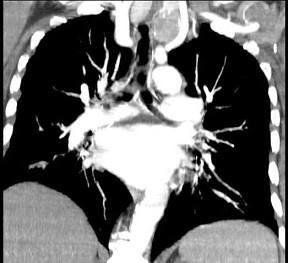

问题 40岁,女,发现颈部肿块,随吞咽上下移动,触之无搏动,咳嗽、气喘一周,请结合CT图。检查选择最可能的诊断 ( )

选项 A、无名动脉伸展扭曲 B、淋巴瘤 C、胸内甲状腺瘤 D、无名动脉瘤 E、胸腺瘤

答案 C